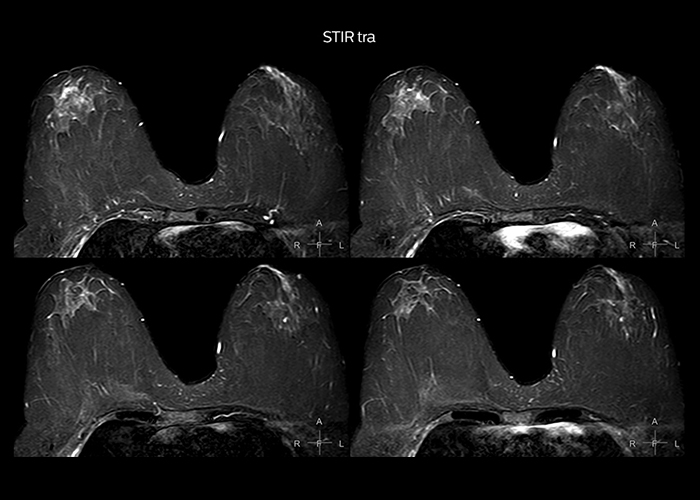

“On average, we scan about 80 patients per day, but on some days we scan well over 100 patients. The scanner is in use 7 days per week, operated 20 hours per day on week days and 8 hours per day in the weekend,” Mr. Tuna says. “To avoid coil changes we plan examinations of similar anatomies back to back, such as head and spine. Multiva helps us here a lot because coils don’t need to be changed frequently. Moreover, thanks to parallel imaging technology and 16-channel HeadSpineTorso and 8-channel MSK coils we are able to achieve excellent image quality. In this way Multiva helped us to increase both image quality and productivity.” “Neurological cases, such as brain and spine imaging, represent the largest share in our MR scanning, followed by musculoskeletal cases. In general, we use simple and basic imaging protocols. But occasionally, we use advanced techniques for problematic cases if necessary.

“Since we have Multiva, we have improved our workflow, because it has been so easy for our operators to learn and use Multiva. Our operators notice that the coils are lightweight and coils don’t need to be changed frequently. The user interface is easy to use. Features like this help us to scan a high number of patients. For instance, the musculoskeletal coils can be used interchangeably, and due to the user-friendly interface, the number of mistakes such as, for example, correct coil element selection has decreased significantly, because the system does it automatically by itself.” “Most important, Multiva satisfies our clinical imaging needs very well,” says Mr. Tuna. “Many features of Multiva have become similar to the Ingenia system. Even in more complex imaging such as abdominal and cardiac, the image quality and performance of Multiva is better than we expected. General surgeons and physicians from our hospital’s internal medicine department prefer to refer to us because of this.”

“Overall, Multiva provides what we need in term of patient needs and even potential needs,” says Mr. Tuna. “It allows us to scan a high patient volume and image a large variety of anatomies and conditions.” “Our goal is to achieve uncompromising quality based on universal standards, while solving clinically complex cases. Our Multiva scanner allows high productivity with fast imaging time, and allows us to make confident diagnoses in a broad range of cases.” “It’s an excellent multi-purpose scanner that satisfies all our MR imaging requirements in the hospital,” he concludes.